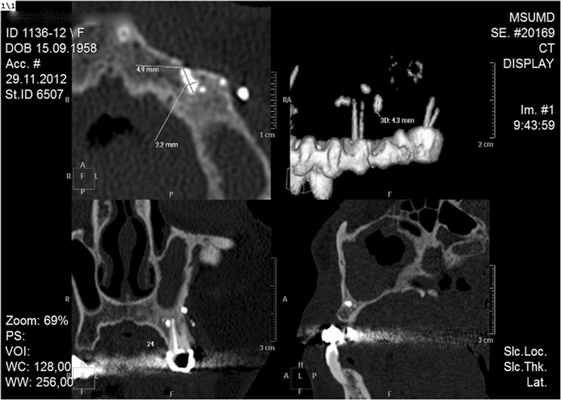

При анализе МСКТ-исследования на уровне верхушки щечного корня зуба 25 в мягких тканях, прилегая к вестибулярной кортикальной пластинке челюсти, было обнаружено скопление пломбировочного материала диаметром около 2,5 мм и аналогичное скопление диаметром

5 мм, на 3,8 мм кзади от вышеописанного. Кроме того, у верхушки небного корня зуба 25 внутрикостно визуализируется скопление пломбировочного материала общим размером 4,9×2,2×3,2 мм (рис. 1). Рисунок 1. Больная П. МСК-томограмма верхней челюсти в саггитальной, коронарной и боковой проекциях. В левой ВЧП визуализируется пломбировочный материал, выведенный за верхушку корня при лечении 25-го зуба. Фрагменты пломбировочного материала в левой ВЧП.

На основании жалоб пациентки на чувство заложенности левой половины носа, дискомфорт в лобной и подглазничной областях слева, внешнего осмотра (незначительный отек щечной области слева, слабо болезненная пальпация подглазничной и щечной областей слева), а также дополнительных методов исследования (ОПТГ, МСКТ-исследование) поставлен диагноз: хронический одонтогенный верхнечелюстной синусит слева. Инородное тело в верхнечелюстной пазухе слева. Состояние после ранее проведенной эндоскопической левосторонней гайморотомии. Больной было проведено оперативное вмешательство в объеме повторной гайморотомии по Колдуэллу-Люку с забором содержимого пазухи. Во время операции из пазухи были удалены полипозно измененная слизистая оболочка, мелкие частицы пломбировочного материала, а также основной фрагмент размером 2×4 мм (рис. 2). Рисунок 2. Та же больная. МСК-томограмма в коронарной проекции до операции. Объем левой ВЧП уменьшен за счет воспалительной гипертрофии слизистой оболочки, стенки пазухи утолщены, склерозированы. Присутствует послеоперационный дефект верхних отделов медиальной стенки в левой ВЧП. Определяется скопление пломбировочного материала. Проведено гистологическое исследование, по данным которого обнаружены мелкие полиповидные кусочки слизистой, выстланные местами эпителием типа респираторного, местами - плоским, местами эпителий слущен, в подлежащих слоях - фиброзная ткань с хронической выраженной воспалительной инфильтрацией, с преобладанием лимфоцитов. Морфологическая картина хронического полипозного синусита.